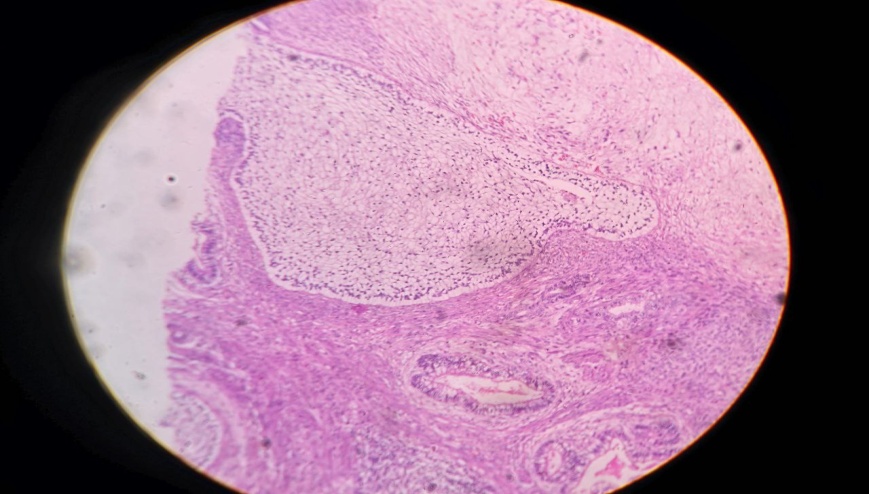

In histopathology, a diagnosis of mixed germ cell tumor was offered with predominant polyembryoma (75%) (fig. 4 and 5)and immature teratoma (25%) (fig. 3) components. The tumor was limited to one testis without any capsular invasion, lymphovascular invasion, or pelvic lymphadenopathy. Immunohistochemistry (fig. 6) confirmed the diagnosis, and the patient was on adjuvant chemotherapy. The patient is under regular follow-up.

Fig. 3: Microphotograph showing teratoma component

Fig. 4: Microphotograph showing polyembryoma component

Fig. 5: Microphotograph showing polyembryoma component